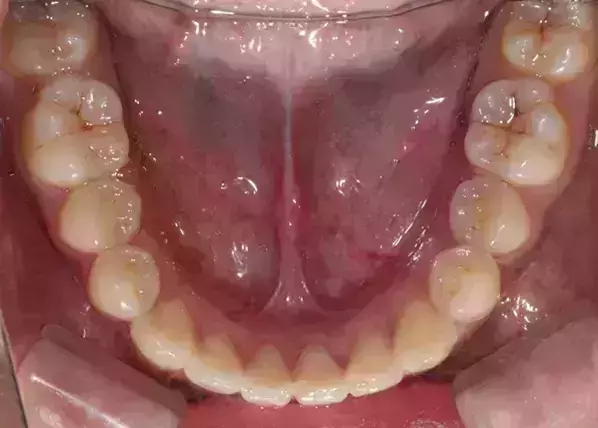

Damon 病例分享:安氏 II 類二分類露齦笑的矯治(董一磊)